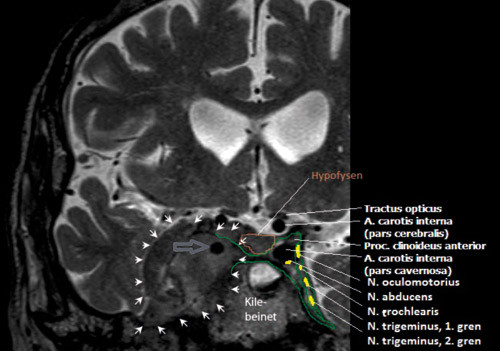

En mann i 70-årene ble utredet for kronisk høyresidig hodepine. Bortsett fra et hengende øyelokk og lett anisokori, typisk for Horners syndrom, ble det ikke påvist nevrologiske utfall. Cerebral MR avdekket en tumor (pilhoder) i høyre sinus cavernosus.

Sinus cavernosus (grønt omriss av venstre side) utgjør et venøst rom dannet av durale folder på hver sin side av kilebeinet og sella turcica, som ligger på øvre flate av dette. Et horisontalt segment av a. carotis interna med dets sympatiske pleksus i adventitia følges tett av n. abducens gjennom denne kanalen på hver sin side av hypofysen, der de bades i blod. I en normal sinus fremstår den laterale veggen som konkav. I den ligger flere hjernenerver (n. oculomotorius, n. trochlearis og n. trigeminus).

Hos denne pasienten er høyre a. carotis interna (pars cavernosa) konstringert (pil) og laterale vegg av sinus cavernosus konveks. Hodepine samtidig med Horners syndrom indikerer at 3. ordens okulosympatiske nevroner (i praksis de fibrene som forløper langs a. carotis interna) er affisert. Kombinert med parese i n. oculomotorius, n. trochlearis, n. trigeminus og spesielt i n. abducens skal det alltid gi mistanke om lesjon i sinus cavernosus. Tumors størrelse tatt i betraktning er det påfallende at det kun foreligger et Horners syndrom hos denne pasienten.